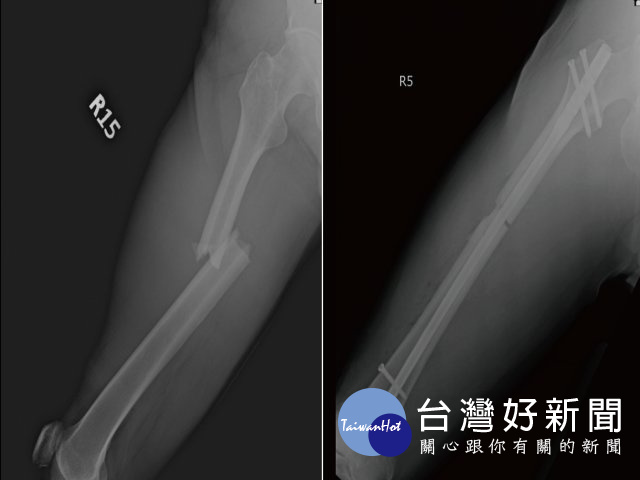

光田綜合醫院骨科王稚暉表示,王先生送抵急診檢查發現他三肋骨骨折、右腿股骨骨折、肝撕裂傷,合併有腹腔出血的狀況,院方當時緊急召集急診、一般外科、胸腔外科及骨科醫師共同治療下,手術縫合額頭傷口、股骨微創骨折復位固定,並給予輸液、輸血,病況始穩定下來。然考量飛機艙壓,王先生接受醫師建議在台灣多停留休養一周,讓身體有更多時間復原後再搭飛機返國。